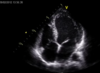

Vilken typ av undersökning är detta?

Ultraljud

Vilken vy?

Var sätter du givaren?

Apikal 4-rumsvy (givare vid iktus)

Givaren vid vänster sida över iktus

Vad ser du?

Hur rör sig hjärtat vid kontraktion på bilden?

Vänster kammare uppåt höger

Vänster kammares bas rör sig uppåt mot spetsen